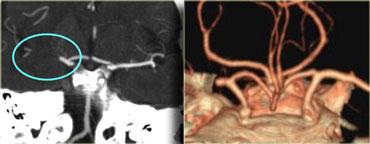

CTA và CT Tưới máu

Sau khi chẩn đoán nhồi máu não, bạn cần xác định mạch máu nào bị tổn thương bằng cách thực hiện CTA.

Trước tiên hãy xem các hình ảnh bên trái và cố gắng phát hiện bất thường.

Sau đó tiếp tục đọc.

Các phát hiện trong trường hợp này rất tinh tế.

Có một vùng giảm tỷ trọng nhẹ ở vỏ não đảo bên phải, đây là vùng chúng ta luôn xem xét đầu tiên.

Trong trường hợp này, hình ảnh gợi ý nhồi máu não, nhưng đôi khi ở bệnh nhân cao tuổi có bệnh lý chất trắng (leukoencephalopathy) thì rất khó phân biệt.

CTA đã được thực hiện (xem hình tiếp theo).

Bây giờ chúng ta có thể tự tin với chẩn đoán nhồi máu MCA.

Trong trường hợp bên trái, đầu tiên CT không tiêm thuốc được thực hiện.

Nếu có xuất huyết, thì không cần thực hiện thêm khảo sát nào.

Trong trường hợp này, CT bình thường và CTP được thực hiện, cho thấy khiếm khuyết tưới máu.

CTA sau đó được thực hiện và phát hiện bóc tách động mạch cảnh trong trái.